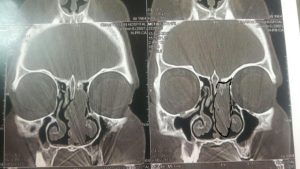

2. سی تی اسکن

تشخیص به وسیله این روش تصویربرداری دقیق تر از سایر روشها می باشد زیرا میزان درگیری استخوان از این طریق نشان می دهد. همچنین برای تشخیص تومور در اطراف مغز از این روش استفاده می شود.

این عکس ها متعلق به خانمی ۵۲ ساله با سابقه گرفتگی بینی از چند سال قبل و نیز سابقه جراحی پولیپ در ۱۰ سال گذشته می باشد در بررسی بالینی نکته دیگری جز توده ای به ظاهر پولیپ مانند در بینی نبود. محل کلی تومور با خط مشکی مشخص شده است

که در تصویر برداری با سی تی اسکن بینی و سینوس نمای موجود شک به این نوع پاپیلوم را برمی انگیخت که طی عمل جراحی اندوسکوپیک و کمک مداوم سر جراحی از همکاران پاتولوژیست وجود این توده ثابت گردیید. و متاسفانه محل پیدایش و منشا اولیه آن در قاعده جمجمه و در محل نازک ترین قسمت استخوان بین بینی و سینوس ها و مغز به طور عملی محرز گردید و این نایحه به طور کامل با کمک ابزارهای خاص تراشیده شده و عمل با اطمینان از برداشت کامل بدون آسیب و صدمه به عناصر حیاتی نظیر مز خاتمه پیدا کرد.